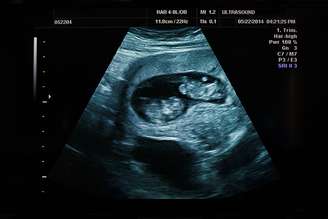

Foto: Xataka

Um caso inédito na medicina surpreendeu pesquisadores brasileiros e chamou a atenção da comunidade científica: uma brasileira de 35 anos, identificada como Ana Paula Martins, descobriu que parte de suas células carrega o DNA de seu irmão gêmeo. Embora seu corpo apresente todas as características genéticas femininas, como útero e ovários funcionais, o sangue dela possui cromossomos masculinos (XY), enquanto o restante do corpo apresenta células com cromossomos femininos (XX). O caso foi investigado e conduzido no laboratório Fleury, Hospital Israelita Albert Einstein e Hospital das Clínicas da USP, e é considerado inédito na medicina mundial.

A medicina está sempre surpreendendo com descobertas inéditas e casos raros que nunca foram vistos anteriormente. No Brasil, o caso de Ana Paula, que carrega o material genético do irmão nas células do sangue, surpreendeu os médicos.. A investigação teve início em 2022, após Ana Paula sofrer um aborto espontâneo e realizar uma série de exames para descobrir o que havia ocorrido, entre eles um teste genético.

O resultado, no entanto, intrigou os médicos: enquanto o DNA de sua pele e outros tecidos revelava cromossomos XX, típicos do sexo feminino, o sangue de Ana Paula apresentava cromossomos XY, associados ao sexo masculino. Após a descoberta, os médicos revelaram a Ana Paula que ela carrega em seu sistema sanguíneo células idênticas às do irmão gêmeo, um acontecimento que nunca havia sido ...